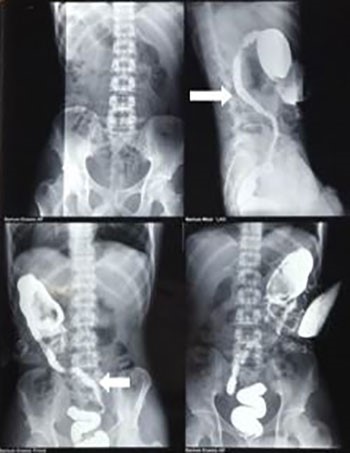

Emergency diverting loop transverse colostomy was done proximal to the transition zone at the splenic flexure. Biopsy from the transition zone revealed nonspecific colitis with normal ganglion cells. Barium contrast study, done after colostomy, revealed a long segment narrowing extending from the splenic flexure to the rectosigmoid junction (Figure 2).

Figure 2. Barium contrast study showing segmental narrowing from splenic flexure to rectosigmoid region (indicated by arrows) with proximal dilatation.